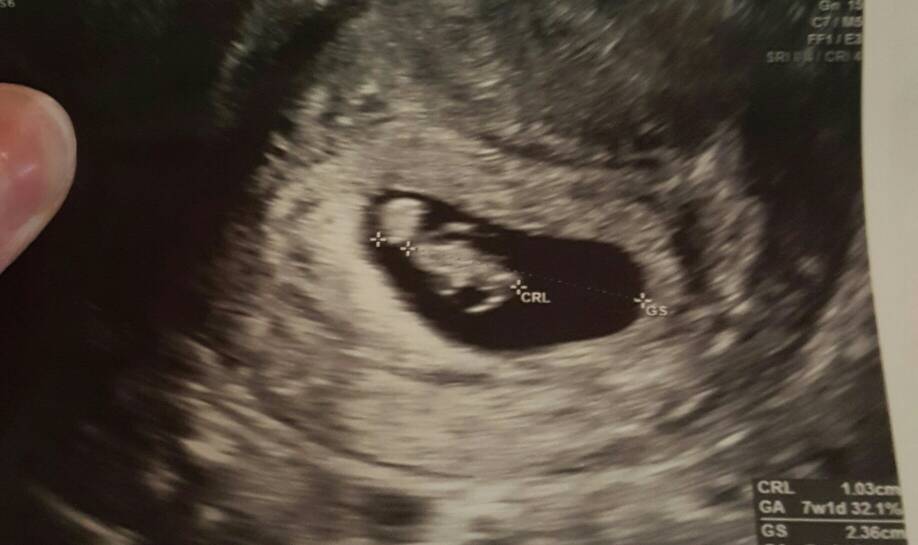

Duzo wrzucacie zdjec to moze i ja ie pochwale moim kochanym pokraczniakiem z soboty ;-)Zobacz załącznik 781883